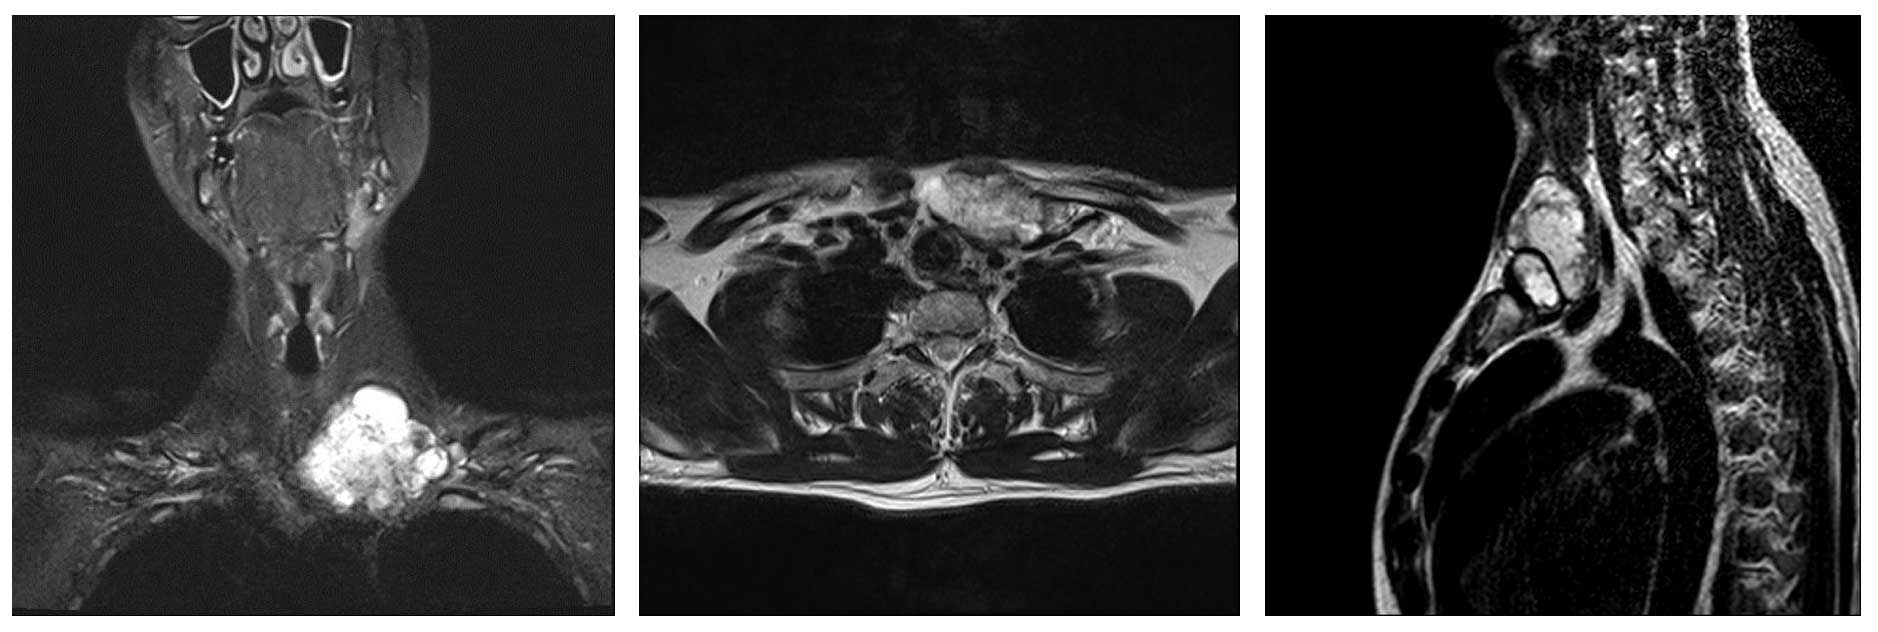

Ameliyat Öncesi: MR’da sol klavikula yerleşimli düzensiz sınırlı heterojen yumuşak doku kitlesi görülmekte.